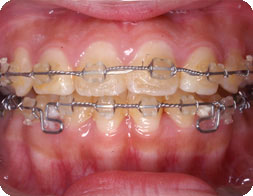

ブラケットによる歯科矯正治療の手順

D.B.S(ダイレクト・ボンディング・システム)による矯正歯科治療の手順です。

ベーシックには、前歯部に透明なブラケットを使用し、D.B.S(ダイレクト・ボンディング・システム)にて矯正治療をしています。 ほぼ、月に1回の調節にて歯並びを直し最後に装置を外します。上下顎の4前歯にはできるだけ後に装置を付けるようにし、審美性には特に気をつけております。